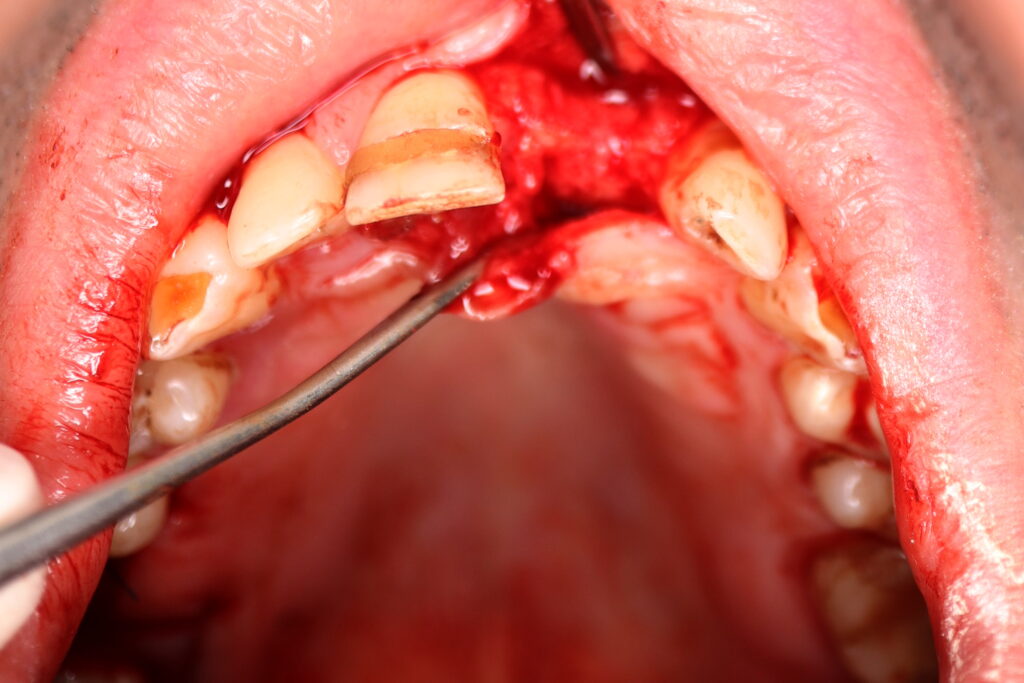

Процесс работы

Что было сделано:

Лечение состояло из двух этапов: хирургический и ортопедический. Длилось 4 месяца.

Были установлены 4 имплантата Straumann BLT. На верхней челюсти в области зуба 2.1 в одно посещение был установлен имплантат и изготовлена временная коронка.

Также в данной области выполнена пластика десны.

хирургический этап

Это фото может содержать тяжелый для восприятия контент